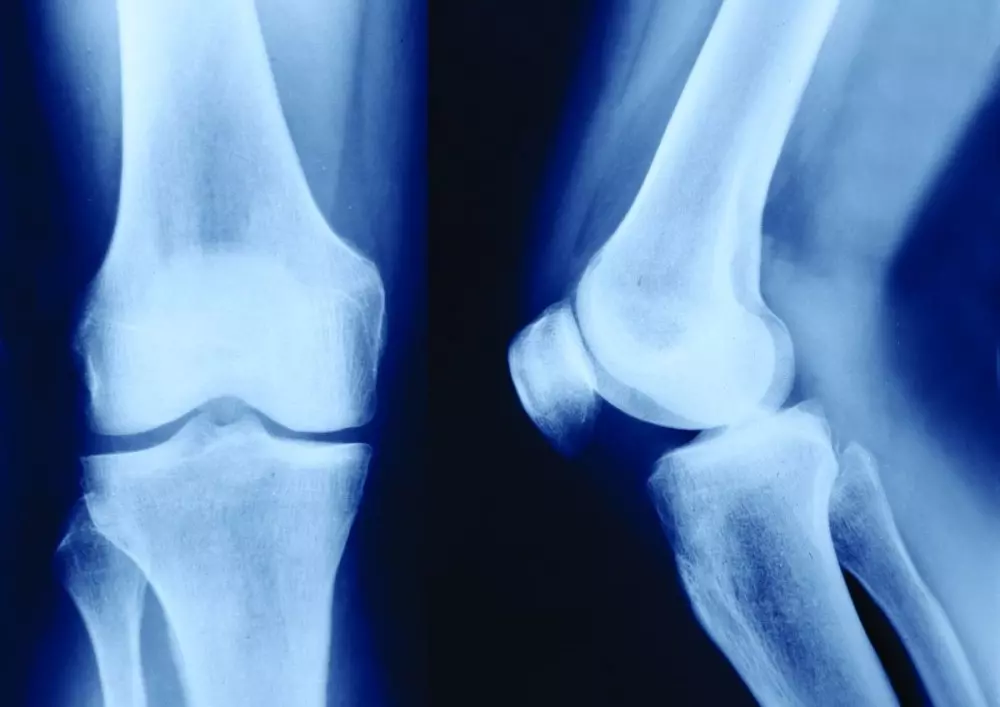

Koncepcja Maitland w badaniu stawu kolanowego

Tym razem koncepcja Maitland pojawia się na łamach naszego czasopisma w kontekście badania i terapii stawu kolanowego. Najczęstszą dolegliwością tego obszaru jest uszkodzenie więzadeł, które powoduje niestabilność strukturalną stawu. Prezentujemy opis badania funkcjonalnego z wykorzystaniem koncepcji Maitland z uwzględnieniem faktu, że badanie płynnie przechodzi w takim wypadku w terapię.